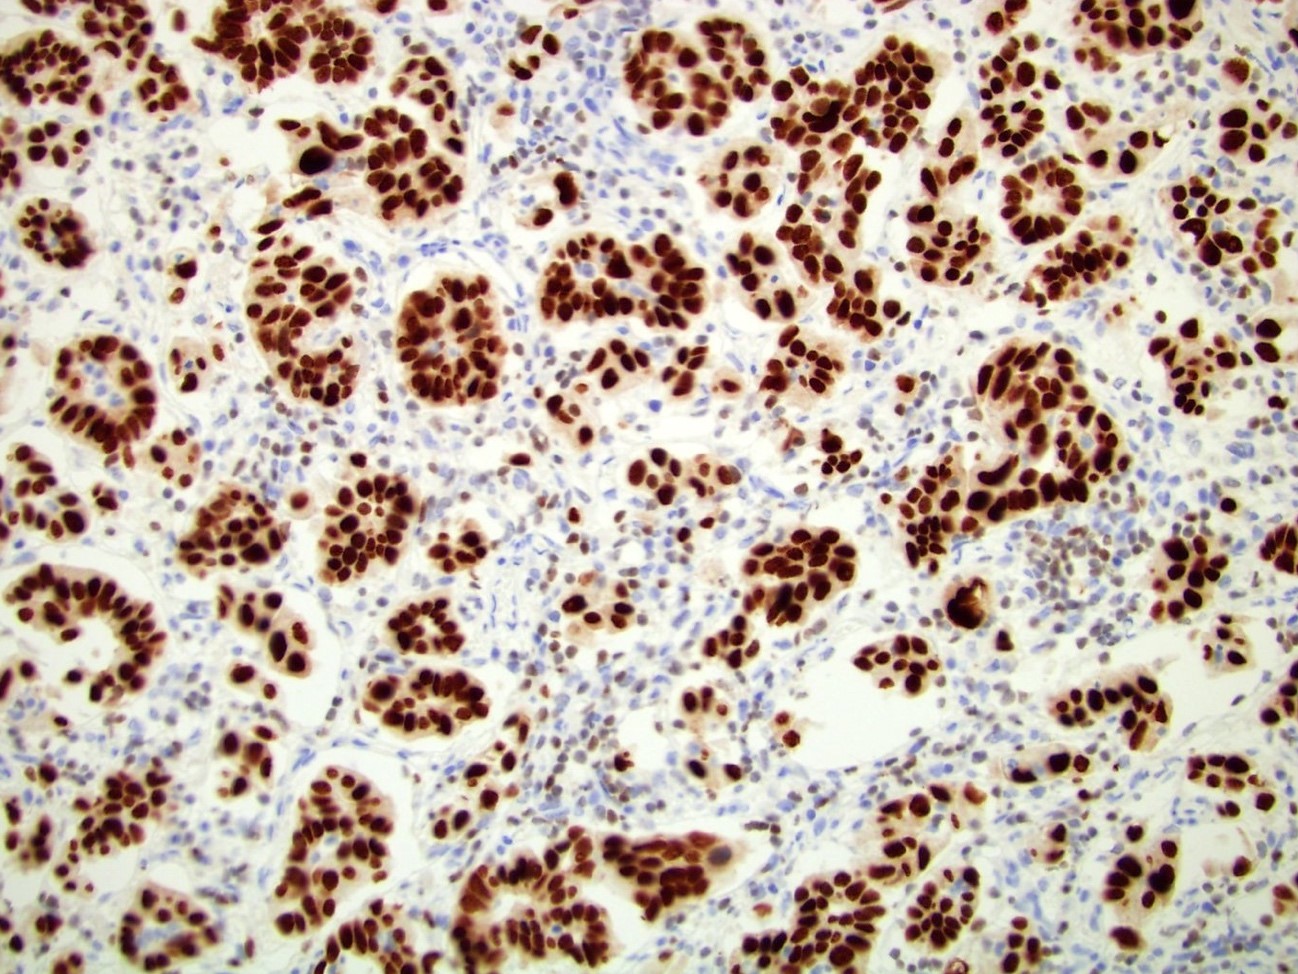

Microscopic (histologic) images

Contributed by Emily S. Reisenbichler, M.D., Andrey Bychkov, M.D., Ph.D., Maria Tretiakova, M.D., Ph.D. and Debra Zynger, M.D.

Positive staining - tumors

- Breast cancer, invasive (72 - 94%) (Mod Pathol 2010;23:654, Am J Clin Pathol 2012;138:57), well differentiated > poorly differentiated; more sensitive than GCDFP-15 and mammoglobin in staining of metastatic breast carcinoma (Ann Diagn Pathol 2015;19:6)

- Primary and metastatic urothelial carcinoma (67 - 93%) (Am J Surg Pathol 2007;31:673, Am J Surg Pathol 2013;37:1876)